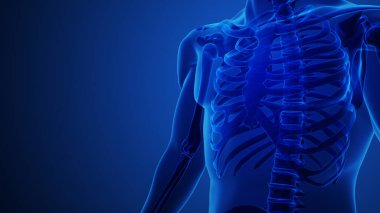

Mavi arka planlı Omuz Eklem Ağrısı

SporresimlemeİnsanSağlıkİlaçdikkatDoktorKemikSınavHastaFizikselkolStresgövdeterapiBoyunHastalıkuygunlukegzersizbiyolojiBilimSorunkırıkiyi değilOmuzAcıKasomurgaEklemİskeletTeşhisanatomiekstremiteKas gücüyineleyiciAmeliyatTravmaAğrıKemik erimesiYaralıkronikRomatizmaiskeletiltihabıArtritBurkulmaUyluk kemiğiSağlıklı yaşam tarzıSağlık hizmetleriBenzer İçerikler